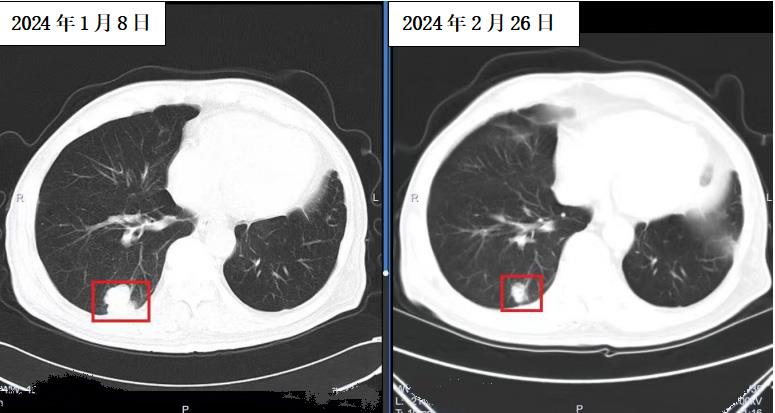

患者影像资料对比

杜爷爷在放疗后一月余后复查,CT示肿瘤明显缩小,达到71%以上,疗效显著,后期预估可能达到CR诊疗标准。